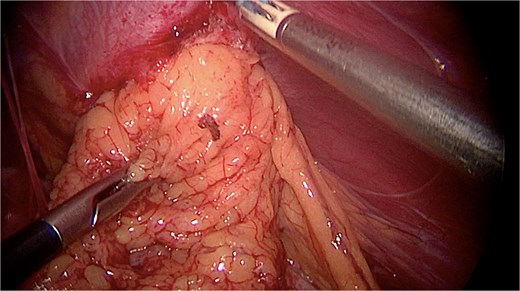

Under general anesthesia, a laparoscopy was made. Intraoperatively, a large diaphragmatic hernia was present with herniation of the omentum (Fig. 3). No transverse colon was found in the hernia, nor were signs of bowel occlusion documented. The content of the hernia was reduced into the peritoneal cavity after performing adhesiolysis and checking organ vitality. The hernia cavity was totally extra-pleural. The parietal pleura was localized cranially, and no expansion was documented even after pulmonary recruitment. The defect in the diaphragm was sutured with PDS 1 go-and-back suture (Stratafix) (Fig. 4) and then covered by a biosynthetic prosthesis (Phasix Mesh), fixed by AbsorbaTack and cyanoacrylate glue (Fig. 5). An intra-abdominal drain was placed. Following the surgery, the patient recovered well and was discharged on the fourth postoperative day (Fig. 6). No postoperative complications occurred. The postoperative imaging control was normal. At the six-month follow-up, the patient showed no signs of recurrence.